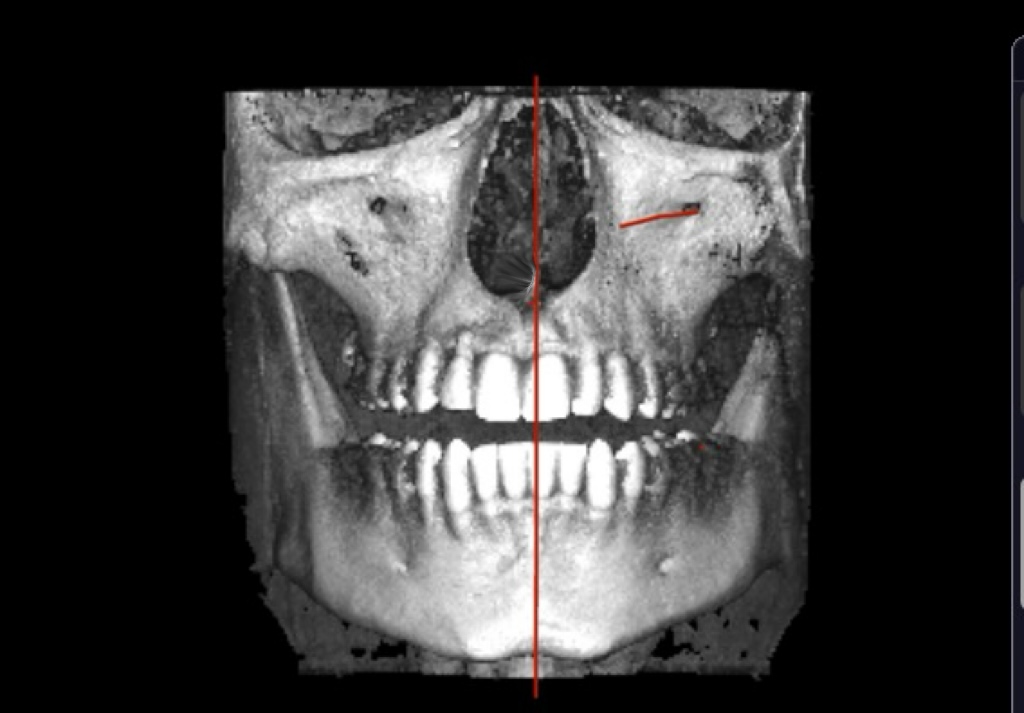

This is how it looks when i try ( and fail) to edit the midline towards center of the face

IMG 4806

seems to be centered, it's just the alveolar bone playing tricks with you head, your teeth are a lil overcrowded and the "midline" in the teeth has "shifted" (thankfully because of the xray you can see that with braces a clear aligner or even a toothborne expander you could fix your overcrowded lower teeth and move the "mid-line" to the right spot, your occlusion doesn't follow the "guide lines" of the bones also I notice that the upper jaw seems to be inlign with the "midline"(teeth and the base of the nasal cavity as you can see in the image)

The alveolar bone in the upper jaw seems to be shifted